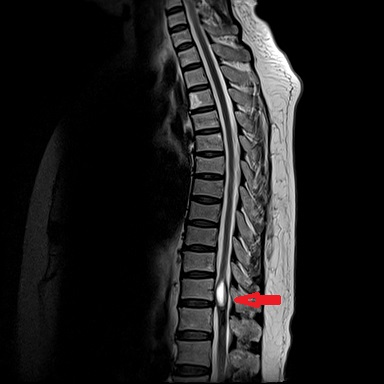

患者康婆婆(化名)今年已近70岁,因“右下肢麻木5+月加重伴疼痛3+月”前来医院治疗,行腰部核磁检查发现胸11椎体平面脊髓内囊性占位,考虑室管膜瘤的肿瘤性病变。患者下肢长期麻木伴疼痛,经神经外科医疗团队研究讨论,为患者行了微创的胸椎椎管骨质切开和脊髓内肿瘤病变的切除手术治疗,切除了患者的肿瘤后,患者下肢肌力和麻木感明显改善。

手术前检查